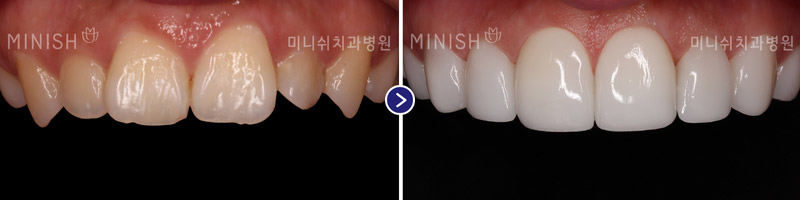

Color Enhancement

Color Enhancement

Color Enhancement